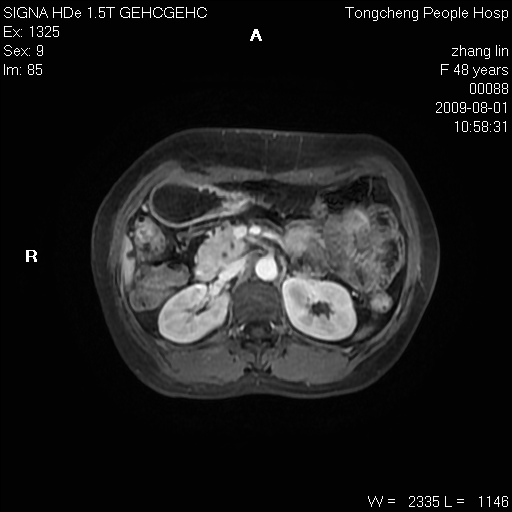

女,48岁。健康体检,彩超发现右肾占位性病变。平素健康。

临床诊断:右肾占位性病变,性质待定(囊肿?肿瘤?)。

上中腹部mr平扫+增强扫描,图像如下:

右肾上极见一类圆形病灶,t1wi呈等信号t2wi呈等高混杂信号,三期增强无强化,边界清---考虑囊肿出血。

同反相位均表现为等信号,病变无强化,考虑含蛋白的囊肿可能,弥散加权相或许有些帮助,

肝囊肿

慢性胆囊炎